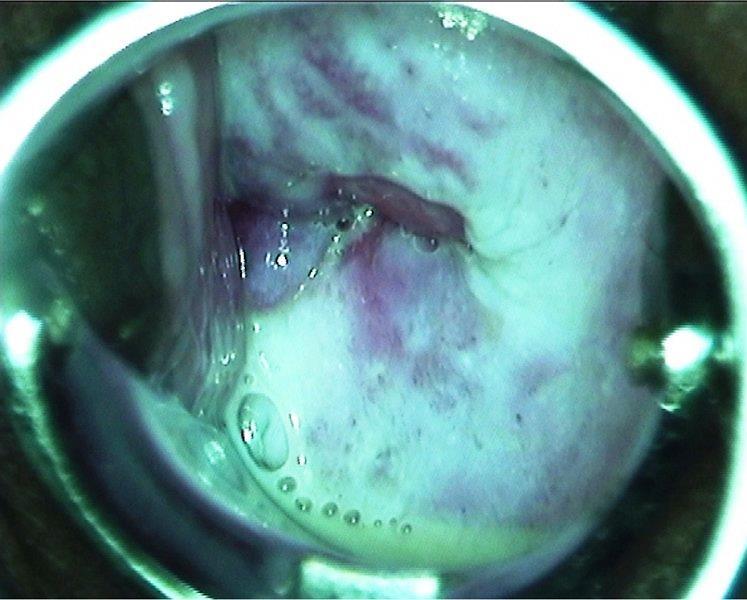

Aspecto histopatológico da infecção do epitélio esofágico por Candida albicans (à esquerda) e da epiderme por Trichophyton spp. (à direita) à coloração PAS (periodic acid-Schiff).